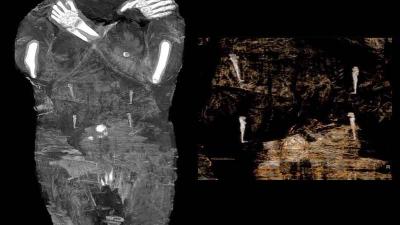

तेव्हा या ममीची टेस्ट केली गेली नव्हती. त्यामुळे असं मानलं जात आहे की, यात पुरूष पुजाऱ्याची ममी आहे. मारजेनाने सांगितले की, आम्ही एक्स-रे आणि कॉम्प्युटर टेस्ट करून हे जाणून घेतलं तेव्हा हैराण झालो. या ममीच्या शरीरावर पुरूषांसारखे अवयव नव्हते.

या ममीचे केस लांब होते आणि महिलांची छाती होती. त्यासोबतच या ममीच्या पोटात एक भ्रूणही होतं. आम्ही पोटात छोटे हात आणि पाय पाहिले. हा शोध आमच्यासाठी हैराण करणारा आणि आनंद देणारा होता. मारजेनाने सांगितले की, आम्हाला असं वाटतं की, ही गर्भवती महिला २० ते ३० वयाची असेल.

ममीच्या पोटातील भ्रूणाच्या डोक्याचा आकार दिसून येतो. ज्यावरून असं वाटतं की, हे भ्रूण २६ ते २८ आठवड्यांचं असेल. वॉरसॉ नॅशनल म्युझिअम येथील ममी प्रोजेक्टमध्ये या ममीची टेस्ट केली गेली. याचा रिपोर्ट जर्नल ऑफ आर्किओलॉजिकल सायन्समध्ये प्रकाशित झाला.